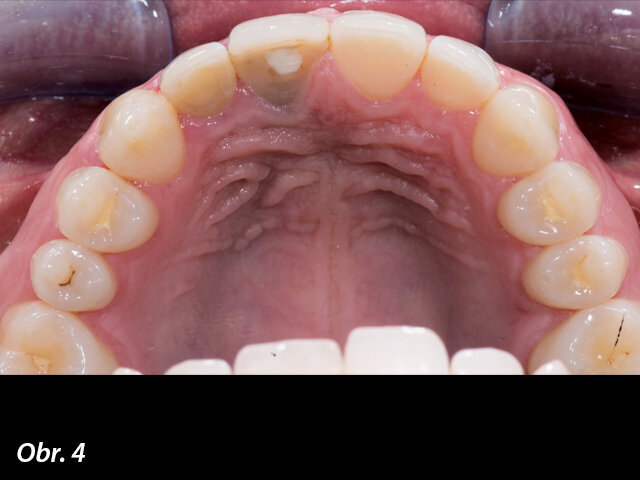

V tomto článku prezentuji klinický případ managementu periimplantátových měkkých tkání pomocí spojení na míru přizpůsobené kolagenní matrix s digitálním postupem při zhotovování provizorní náhrady, a to s cílem dosáhnout adekvátního výsledku ošetření u pacientů s gingiválním úsměvem. Předkládám digitální pracovní protokol, který používám, když potřebuji zachovat původní morfologii měkkých tkání (obrys gingivy a papily) ve frontálních oblastech. Jak je známo, k dosažení optimálního výsledku řešení případů problematické estetiky chrupu je nutno, aby mezi měkkými tkáněmi a protetickými výrobky existovala určitá harmonie: to znamená, že mezizubní papily, obrys gingivy, zubní osy a dominance středních řezáků by měly být mezi sebou navzájem dobře vyváženy (obr. 1).